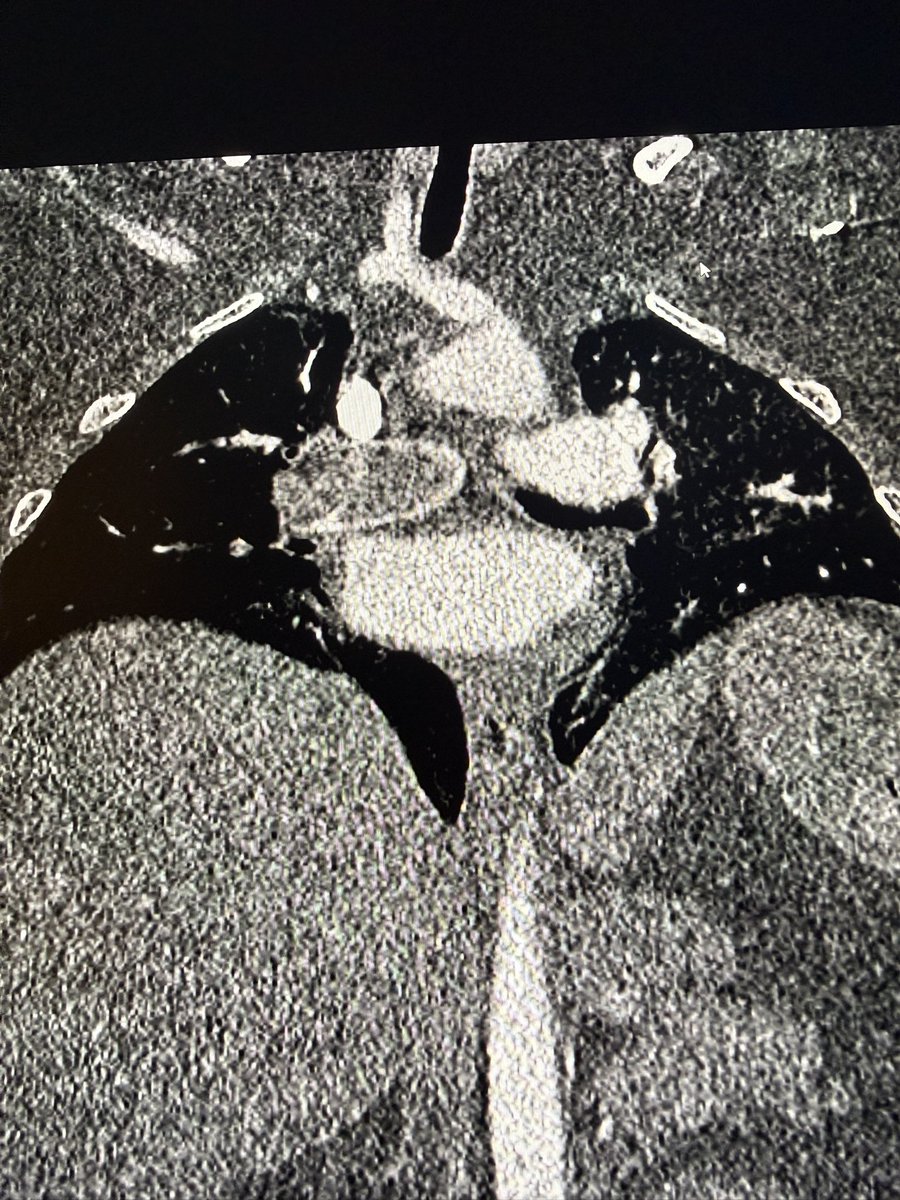

In the spirit of chronic clot (@DrJayMohan) - just pulled out the largest chronic PE I’ve encountered.

Tough situation w/ peds patient, malignancy and prolonged hospitalization with delayed diagnosis.

PA angle also very difficult to deal with.

Well compensated but symptomatic with chest pressure improving immediately.

AC wasn’t going to touch this, guarded prognosis overall but I’d argue better out than in

Controversial? What are your thoughts?